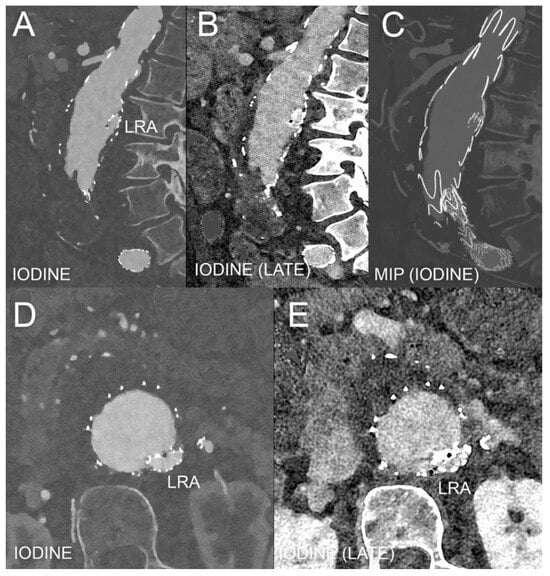

- Kazimierczak, W.; Kazimierczak, N.; Serafin, Z. Review of Clinical Applications of Dual-Energy CT in Patients after Endovascular Aortic Repair. J. Clin. Med. 2023, 12, 7766. [Google Scholar] [CrossRef]

- Kazimierczak, W.; Kazimierczak, N.; Serafin, Z. Quality of virtual-non-contrast phases derived from arterial and delayed phases of fast-kVp switching dual-energy CT in patients after endovascular aortic repair. Int. J. Cardiovasc. Imaging 2023, 39, 1805–1813. [Google Scholar] [CrossRef]

- Ascenti, G.; Mazziotti, S.; Lamberto, S.; Bottari, A.; Caloggero, S.; Racchiusa, S.; Mileto, A.; Scribano, E. Dual-Energy CT for Detection of Endoleaks After Endovascular Abdominal Aneurysm Repair: Usefulness of Colored Iodine Overlay. Am. J. Roentgenol. 2011, 196, 1408–1414. [Google Scholar] [CrossRef]